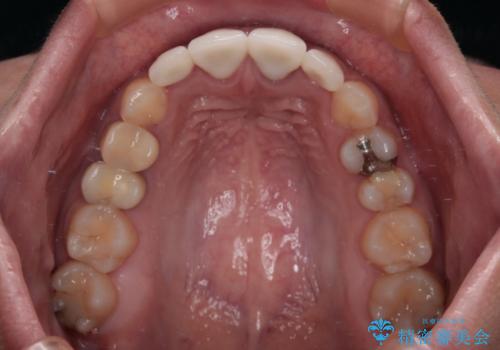

下顎の小臼歯を移動しきるのに2年弱の期間を要することとなり、補綴治療も合わせて2年半ほどの治療期間となりました。

口元の印象が大きく改善し、患者様には大変満足していただけました。